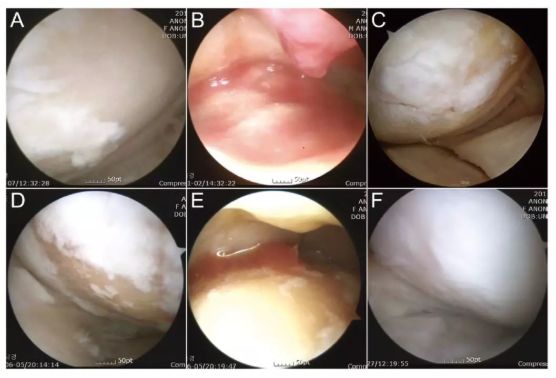

關(guān)節(jié)鏡下評(píng)價(jià) ADSC 移植治療膝骨關(guān)節(jié)炎軟骨損傷

(Am J Sports Med, 2014)

參與者人數(shù):N=35

治療方案:將 3.8*10^6 脂肪間充質(zhì)干細(xì)胞注射到關(guān)節(jié)腔內(nèi),并在治療后約 24-36 個(gè)月測(cè)試結(jié)果。

評(píng)估指標(biāo):IKDC 評(píng)分丨關(guān)節(jié)鏡檢查丨主訴

研究結(jié)果:ADSCs 治療可以顯著改善膝骨關(guān)節(jié)炎,BMI 越高效果越差。

注:上圖中 A-C 為 51 歲男性膝關(guān)節(jié)鏡,D-F 為 54 歲女性膝關(guān)節(jié)鏡。A/D 為治療前,白色示意軟骨,淺黃色示意裸露的骨。B/E 為間充質(zhì)干細(xì)胞注射。C/F 為治療后的關(guān)節(jié)鏡檢查。